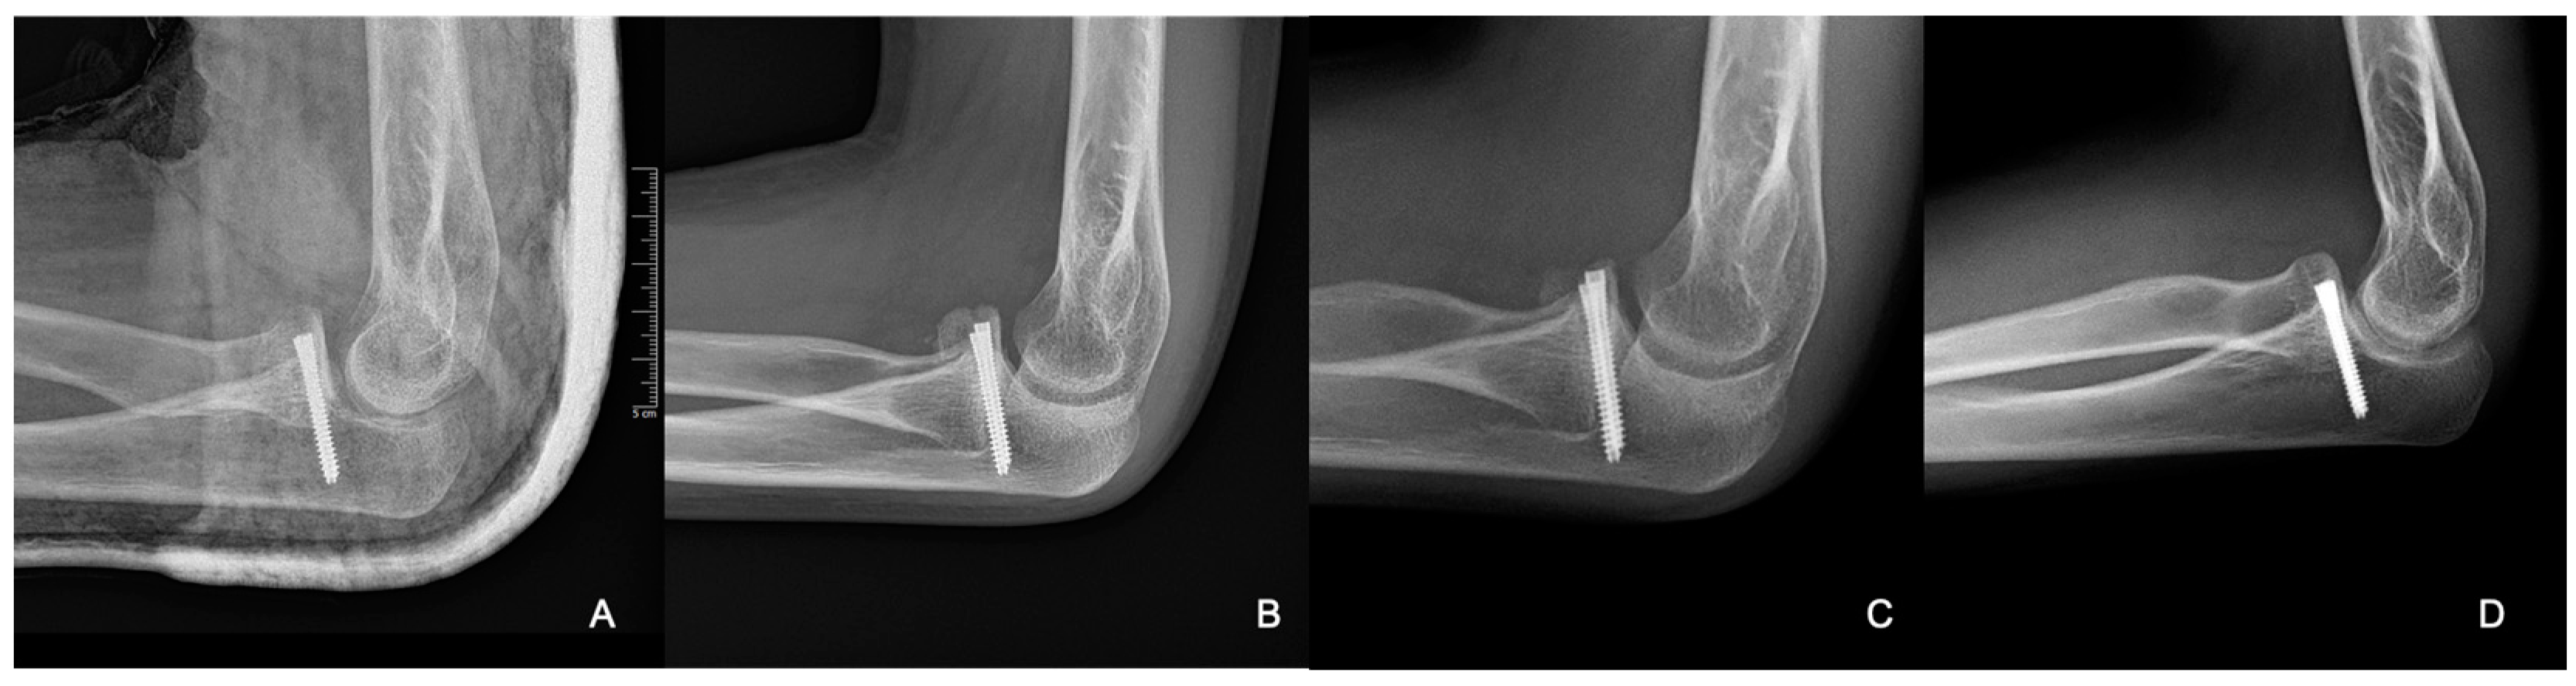

Figure 8.

Radiographic control images from weeks 3 (A), 8 (B), 24 (C), and 40 (D).

From the X-ray imaging, it was seen that the fracture was rebuilt and the coronoid process was stabilized in a good position, with a complete ROM in the elbow joint (Figure 9).